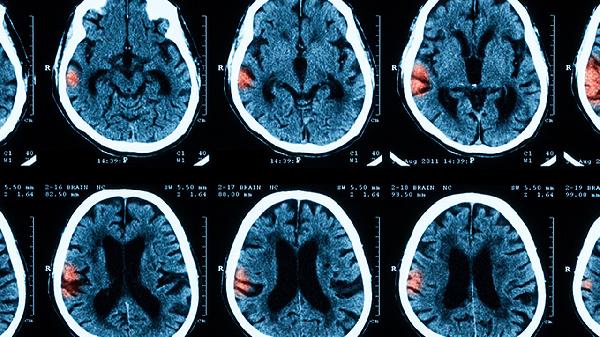

先天脑膜炎患儿出院后需定期复查脑电图和头颅影像学,避免剧烈运动及感染诱发复发。饮食应保证充足蛋白质和必需脂肪酸摄入,推荐深海鱼、核桃等健脑食物。适当进行水疗、音乐疗法等感官刺激训练,家庭成员需学习基本护理技能。疫苗接种需根据免疫状态调整方案,接触感染者需及时预防性用药。心理支持需贯穿整个生长发育期,帮助患儿适应社会功能。